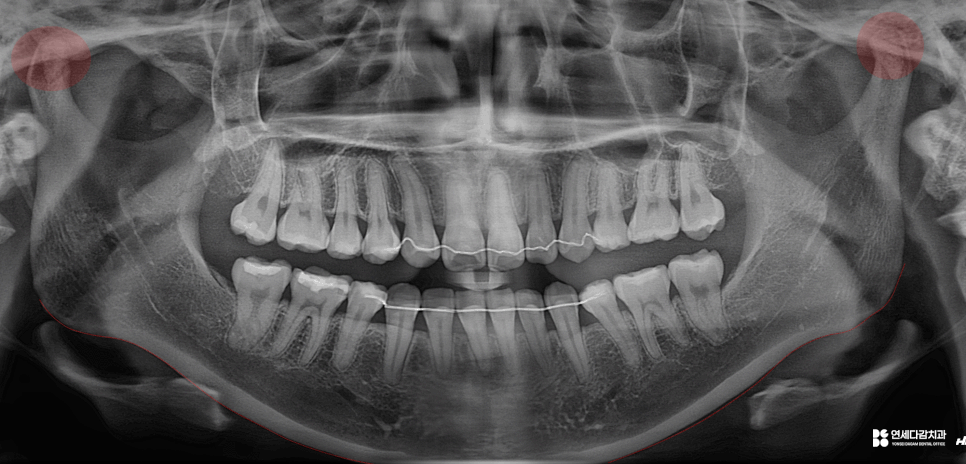

오늘 가락동 치과 에서 소개해 드릴

케이스의 상태를 살펴봤을 때,

26.01.09

턱이 오른쪽으로 쏠리는

편위(deflection)현상이 있습니다.

안면 골격의 비대칭도 일부 발견되지만,

큰 문제가 되는 수준은 아닌 것으로 평가됩니다.